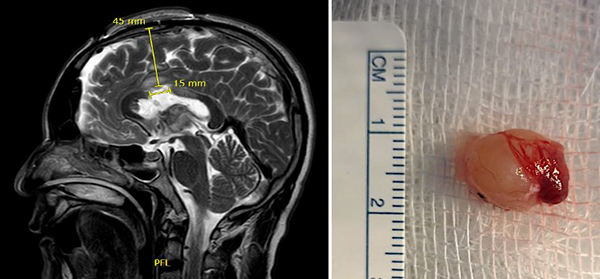

Paciente masculino de 40 años, sin antecedentes patológicos, atendido en nuestra institución por presentar cuadro de 2 años de evolución caracterizado por cefalea holocraneana de moderada intensidad, intermitente. Dos meses previo a la consulta inicial había presentado pérdida de consciencia más un episodio de crisis convulsiva tónico-clónico generalizada. Al examen físico el paciente no presentaba deterioro del sensorio ni déficit neurológico evidente. El resto del examen no mostraba hallazgos relevantes. La resonancia magnética (IRM) evidenció una lesión ovoidea que ocupaba el foramen de Monro, isointensa respecto al parénquima cerebral en las secuencias T1 y T2, de 12x9x9 mm, su margen rostral y dorsal en contacto con el pilar anterior y cuerpo del fornix, respectivamente; con tenue realce a la administración del contraste. En la secuencia de tensor de difusión los diferentes tractos se aprecian con trayecto normal y adecuada disposición de las fibras. Sistema ventricular sin dilatación ni compresiones. Se realizó la exéresis total de la lesión a través de un abordaje interhemisférico transcalloso anterior guiado por sistema de neuronavegación (Figura 1). El curso postoperatorio transcurrió con una hemiparesia braquio-crural derecha transitoria, que cede en días subsecuentes con recuperación total de la fuerza muscular. El paciente fue dado de alta sin déficit neurológico agregado. El examen patológico reportó un quiste coloide. La IRM postoperatoria confirmó la extirpación total de la lesión con cambios postquirúrgicos asociados a craneotomía fronto-parietal derecha (Figura 2). El paciente se encuentra asintomático en seguimiento por la consulta externa.

Figura 1. (A) IRM T2W coronal: ubicación anatómica de la lesión en foramen interventricular; (B) IRM integrada al sistema de neuronavegación, planeación de abordaje quirúrgico.

Figura 2. (A) IRM T2W sagital postoperatoria muestra la ruta de aproximación y longitud de la callosotomía; (B) Imagen de pieza quirúrgica mostrando su exéresis total.